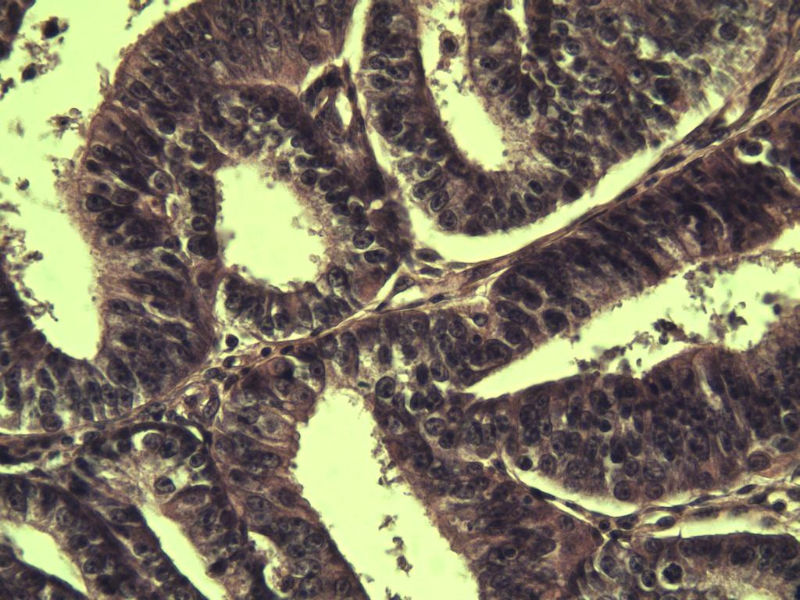

子宫内膜癌?? 会诊结果出了

女 32岁 不规则阴道流血 一年  请各位老师看看 谢谢了

遵义医学院附属医院会诊结果    "复杂性增生伴非典型性 "

补充一下病史 病人10个月前因月经不规则行诊刮 诊断非典型性增生  上了曼月乐避孕环(好像是缓慢释放孕激素的那种),         都用激素治疗大半年了 还是这个样子 我还是觉得是癌  只有追踪一下以后病人的情况吧

高分化子宫内膜样癌

非典型复杂性子宫内膜增生,应了解雌孕激素情况。

非典型复杂性子宫内膜增生,32岁,太年轻了,是不是要考虑她的激素情况?

子宫内膜复杂性非典型性增生,局灶区间质肉芽样(图5)及蜕膜样变,不够癌,建议临床查激素水平并追踪。

从照片看,没看到浸润的地方,我考虑是子宫内膜重度不典型增生。

既“局灶区间质肉芽样(图5)及蜕膜样变”,为何不能报“局灶呈高分化子宫内膜样腺癌改变”?个人理解,报告中所含的“局灶×××”,应该是更高级别的但范围较小或较局限的病变。